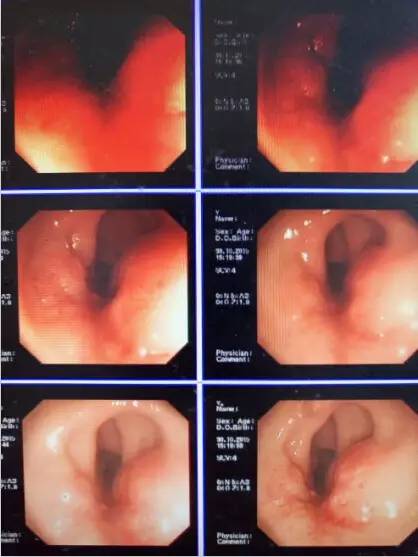

特殊检查:心电图:窦性心律;胸片:正常;肺功能:正常;18-FDG:未见明显代谢异常病灶;心超+心功能:左室舒张功能欠佳,主动脉瓣轻度钙化+左室收缩功能未见明显减弱,左室舒张功能欠佳(EF66%);胃镜:(胃窦)慢性萎缩性胃炎,HP(-);肠镜:直肠:距肛门5-8cm可见菜花状肿块,表面糜烂坏死,伴少量出血,占肠腔1/2圈,并取活检4块。(如图1)11-10肠镜活检标本:(直肠肿块)粘膜间质见小圆细胞浸润,酶标结果:CK+,Sy+,CgA-/+,符合神经内分泌肿瘤。免疫组化:HP(+),CK(+),CgA(-/+),Syn(+),CD56(-),Ki67(指数0.03),LCA(-),CAM5.2(-),CK20(-),Vim(-),HMB45(-),Melanoma(-),SOX-10(-)。

图1